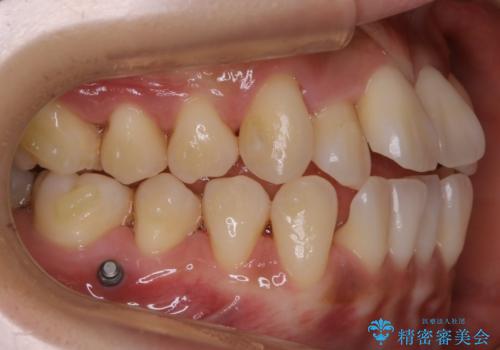

診査の結果、骨の厚みに余裕がなく幅の拡大とIPR(歯と歯の間を削り隙間を作る作業)のみでは歯周病に対する不安が残ることが懸念されたため、マイクロインプラントを用いて奥歯から順にすべての歯を後方移動させる方法によってスペースを作ることとなりました。

歯の遠心移動

歯を奥に移動させてスペースを作る方法を用いる場合、マウスピースの装着時間ならびに装着時の適合度がそれぞれ良い状態で保たれているかどうかが大きく関わってきます。